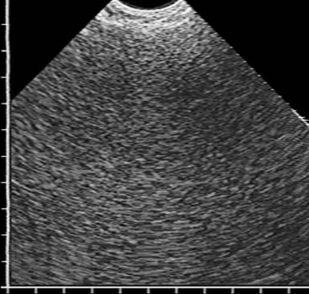

В книге в практическом аспекте изложены вопросы ультразвуковой диагностики опухолей лёгких: показаны возможности и ограничения трансторакальной эхографии при выявлении внутрилёгочных объёмных образований, приведена методика исследования и нормальная эхокартина грудной клетки, подробно освещена ультразвуковая семиотика центрального и периферического рака лёгкого, включая эхопризнаки про# растания опухоли ворганы средостения или грудную стенку. Детально изложены вопросы дифференциальной диагностики онкологической патологии лёгких при синдроме безвоздушной лёгочной ткани и синдроме пристеночного образования. Впервые представлен комплекс симптомов для определения внутри- или внелёгочной локализации пристеночного образования. В отдельной главе рассмотрены субплевральные очаговые образования неопухолевой этиологии: инфаркт лёгкого, очаговый фиброз, жидкостные кисты, артериовенозная аневризма и другие редкие заболевания. Книга иллюстрирована большим количеством эхограмм, отображающих основные диагностические признаки рассматриваемой патологии.